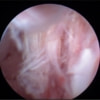

関節鏡検査を実施いたしました。関節鏡検査では、重度の滑膜炎および前十字靭帯の完全断裂が認められました。半月板に損傷は認められませんでした。

関節穿刺を行い、好中球はなく、少数のマクロファージや滑膜細胞が認められるました。膝蓋骨脱臼および前十字靭帯断裂による退行性の関節炎を疑い、関節鏡検査を実施いたしました。関節鏡検査では、重度の滑膜炎および前十字靭帯の完全断裂が認められました。内外側とも半月板に損傷は認められませんでした。